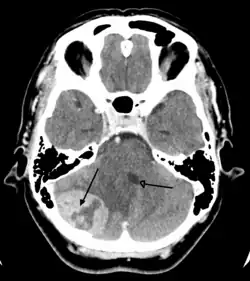

| Brain metastasis in the right cerebral hemisphere from lung cancer, shown on magnetic resonance imaging | |

Secondary tumors of the brain are metastatic and have spread to the brain from cancers originating in another organ. Metastatic spread is usually by the blood. The most common types of cancers that spread to the brain are lung cancer (accounting for over half of all cases), breast cancer, melanoma skin cancer, kidney cancer and colon cancer.[62]